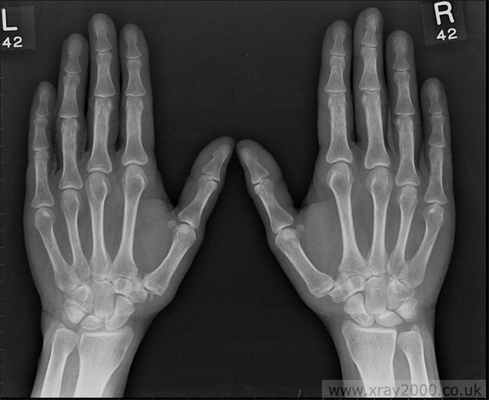

Остеоартроз мелких суставов кисти

Характеризуется следующими клиническими признаками:

- Наличие плотных узелков на боковых поверхностях дистальных межфаланговых суставов (узелки Гебердена) и на тыльно-боковой поверхности проксимальных межфаланговых суставов (узелки Бушара); Образование узелков сопровождается жжением, покалыванием, онемением (после завершения формирования узелков эти симптомы исчезают)

- Боль и некоторая скованность в суставах кисти, уменьшение объема движений.

- Прогностически наличие узелков Гебердена или Бушара является неблагоприятным признаком течения остеоартроза. (эта форма остеоартроза имеет генетическую детерминированность и передается по женской линии).